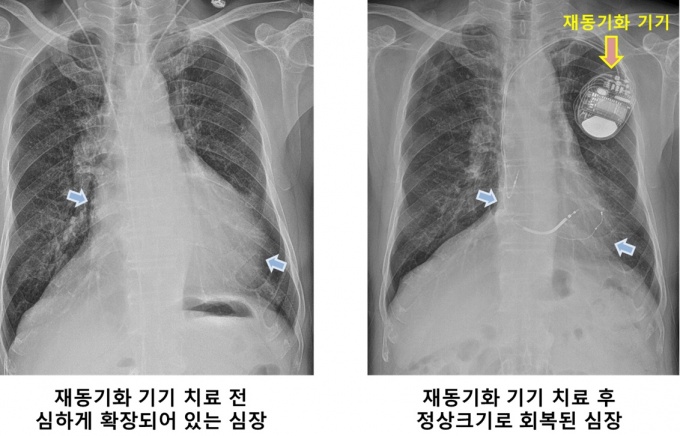

[µ¥Àϸ®¸Þµð ¹Ú¼ºÀº ±âÀÚ] »ï¼º¼­¿ïº´¿ø(¿øÀå ±Ç¿ÀÁ¤)Àº ½ÉÀå³úÇ÷°üº´¿ø ºÎÁ¤¸Æ¼¾ÅÍ¿¡¼­ ±¹³» óÀ½À¸·Î ½ÉÀåÀ絿±âÈ­Ä¡·á 300·Ê¸¦ ´Þ¼ºÇß´Ù°í 7ÀÏ ¹àÇû´Ù.

»ï¼º¼­¿ïº´¿ø¿¡¼­ óÀ½ ½ÉÀåÀ絿±âÈ­Ä¡·á¸¦ ½ÃÀÛÇÑ ¶§´Â 2005³âÀ¸·Î, 2020³â±îÁö ¾à 15³â µ¿¾È 300¸íÀÇ È¯ÀÚ°¡ ÀÌ Ä¡·á¸¦ ¹Þ¾Ò´Ù.

½ÉÀåÀ絿±âÈ­Ä¡·á´Â ȯÀÚ ¸ö ¼Ó¿¡ »ðÀÔÇÑ À絿±âÈ­±â±â¿Í ¿¬°áµÈ Àü±Ø¼±À» ½ÉÀåÀÇ ¿ì½É¹æ°ú ¿ì½É½Ç, ÁÂ½É½Ç ¿ÜÃø º®±îÁö ¼¼ °÷À¸·Î ¹Ð¾î ³ÖÀº µÚ Àü±â¸¦ Èê·Áº¸³» ºñÁ¤»óÀû ½ÅÈ£¿Í ºñ´ëĪÀûÀÎ ½ÉÀå ¼öÃàÀ» ¹Ù·Î Àâ´Â Ä¡·á¹ýÀÌ´Ù.

½Ã¼úÀÌ ¾î·Á¿î ¸¸Å­ Ä¡·á È¿°úµµ ±ØÀûÀÌ´Ù. ½ÉÀå ±â´ÉÀÌ 100Á¡ ¸¸Á¡ ±âÁØÀ¸·Î 50Á¡¿¡¼­ 60Á¡¿¡ ºÒ°úÇÏ´ø ȯÀÚµéÀÌ ÇØ´ç Ä¡·á¸¦ ¹Þ°í ³ª¸é 70Á¡¿¡¼­ 80Á¡±îÁö È£ÀüµÈ´Ù. ÀÌ °¡¿îµ¥ 3ºÐÀÇ 1Àº °ÅÀÇ Á¤»ó ¼öÁØ¿¡ °¡±î¿öÁö±âµµ ÇÑ´Ù.